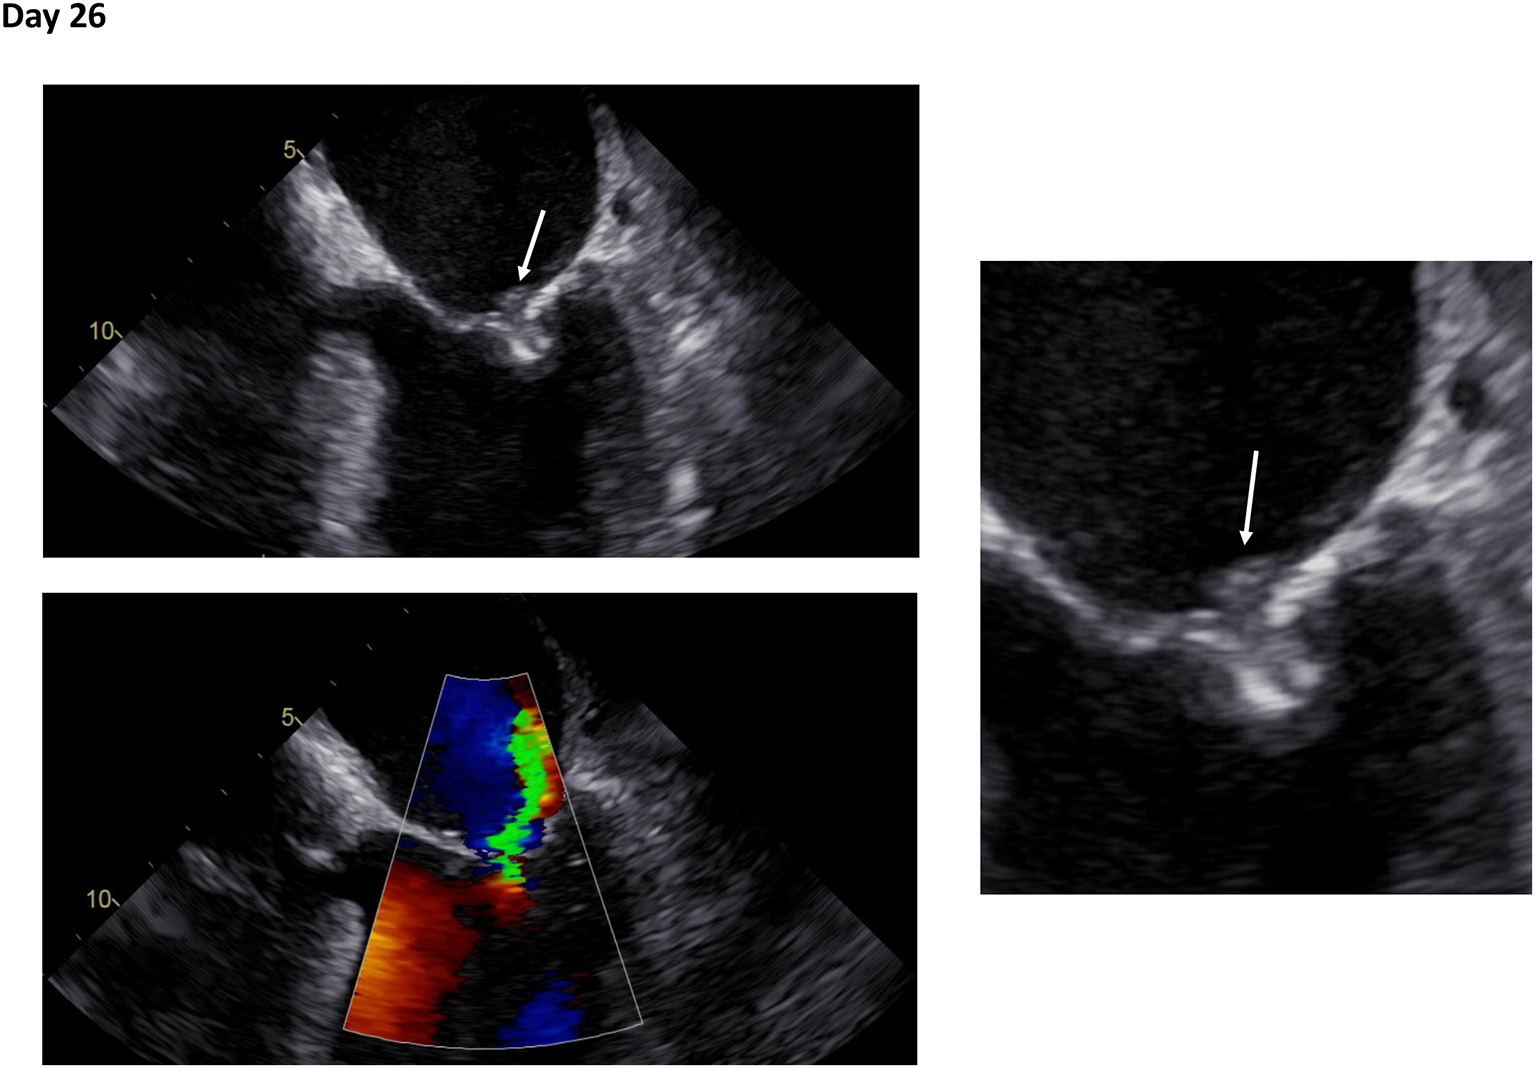

Figure 1

Initial transesophageal echocardiography in recurrent fever and persisting bacteremia. Transesophageal echocardiography at day 26 following mitral valve edge-to-edge repair. Right: Zoom on mitral valve. White arrows indicate an echogenic structure suspicious for vegetation (Day 26: Supplementary Videos 1, 2).

Vasopressors, infusion therapy and fever reduction led to hemodynamic stabilization of the patient. Pneumonia was excluded by a thoracic X-ray and abdominal sonography excluded post-renal kidney injury or an abdominal focus of sepsis. The laboratory results revealed a normal CRP (<0.4 mg/dl) but markedly elevated PCT (63.34 ng/ml), leucocytosis and acute to chronic renal failure, which led to the diagnosis of a sepsis due to urinary tract infection. Early antibiotic treatment with piperacillin/tazobactam 4.5 g tds was started immediately. The urine status proofed a bacterial urinary tract infection. On day 2 catecholamines could be reduced and PCT decreased (41.1 ng/ml), while CRP (18.6 mg/dl) was markedly increased. The initially withdrawn blood revealed repeatedly P. mirabilis bacteremia as causal for the sepsis due to urinary tract infection. Urine culture also confirmed P. mirabilis. The antibiograms of blood and urine culture revealed Ampicillin/Sulbactam, Amoxicillin/Clavulanate, Piperacillin/Tazobactam, Cefuroxim, Ceftriaxon, and Meropenem to be effective antibiotic agents. Following the antibiogram the antibiotic regime was changed to Ampicillin/Sulbactam 3 g tds. After reversal of renal failure and discontinuation of the vasopressors the patient was transferred to the general internal medicine ward. Inflammatory markers decreased. Transesophageal echocardiography (TOE) was performed to exclude infective endocarditis (IE). However, initial TOE interpretation excluded IE, while a small echogenic structure on the PASCAL Ace device was suspicious for vegetation (Figure 1; Supplementary Videos 1, 2). The antibiotics were discontinued, but the patient suffered from decompensated heart failure with peripheral edema and pleural effusion as consequence of the sepsis infusion therapy. Right side pleurocentesis was necessary. At day 35 the patient developed fever and blood cultures again showed P. mirabilis with the same resistogram. CRP and PCT were elevated but no signs of bacteriuria were found in the urine status. Clinical course of recurrent bacteremia with implanted cardiac device in mitral position led to the suspected diagnosis of endocarditis.